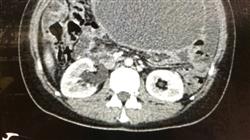

O câncer do ovário é o quarto câncer mais comum de origem ginecológica, porém é o mais letal. A maioria desses tumores se apresenta em estágios avançados da doença, quando a sobrevivência é de apenas cerca de 30% dos casos. Portanto, o conhecimento da fisiopatologia e o diagnóstico precoce da doença é crucial.

É necessário que o médico especialista esteja atualizado sobre os principais aspectos da epidemiologia e do diagnóstico do câncer de ovário, pois a amplitude e a especificidade dos avanços que são publicados e descobertos constantemente sobre o câncer de ovário devem ser levados à prática médica diária.

Este Curso tem como objetivo proporcionar ao profissional uma atualização sobre a epidemiologia, as causas e todo o processo de diagnóstico do câncer de ovário.

Este curso inclui casos clínicos e imagens reais em alta definição para aproximar ao máximo a prática clínica ao desenvolvimento do programa de estudos”